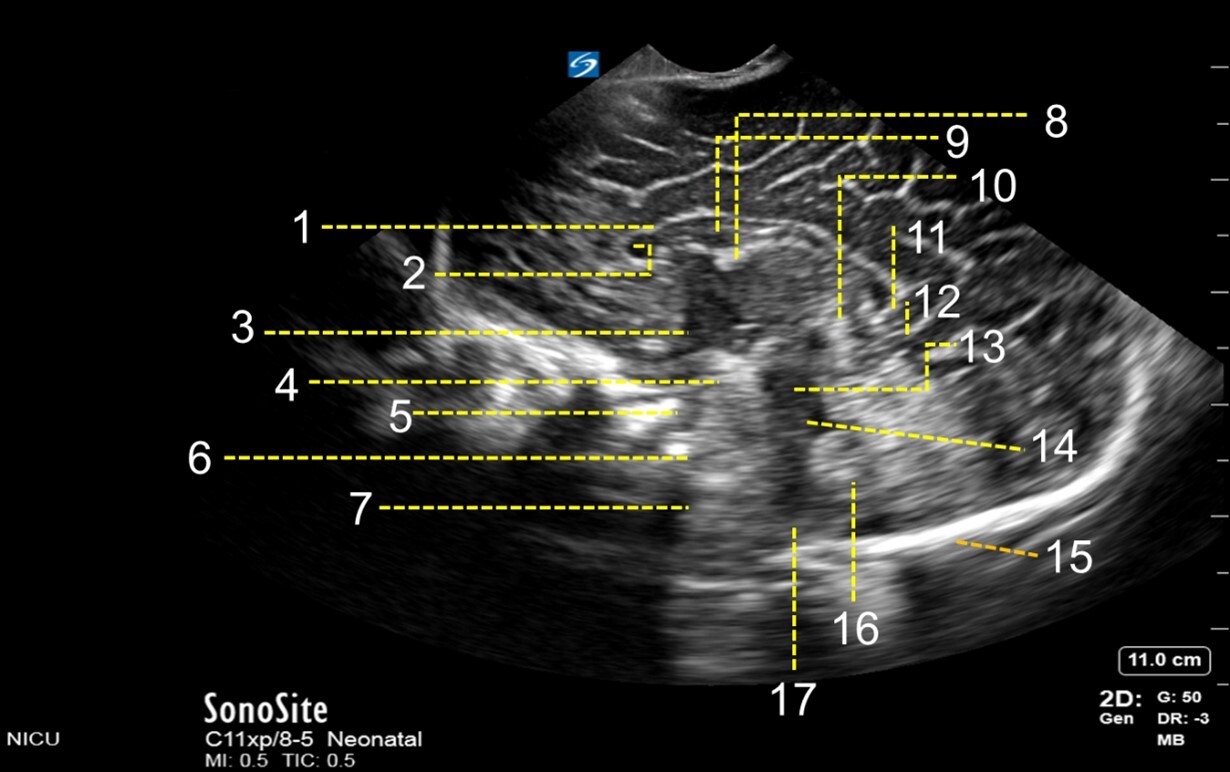

1. Corpus Callosum

2. Cavum Septum Pellucidum

3. 3rd Ventricle

4. Mesencephalon

5. Interpeduncular Cistern

6. Pons

7. Medulla Oblongata

8. Fornix

9. Cavum Vergae

10. Tectal Plate

11. Parieto-occipital Fissure

12. Calcarine Fissure

13. Mesencephalic Aqueduct

14. 4th Ventricle

15. Skull

16. Cerebellar Vermis

17. Cisterna Magna